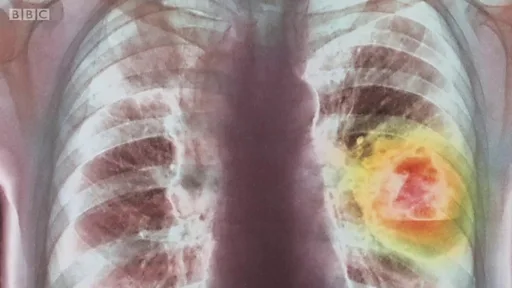

Mientras CRISPR puede ser usada para una variedad de enfermedades genéticas, hay muchas otras compañías que están persiguiendo tipos específicos de cáncer. Hay más de 200 formas de la enfermedad, lo cual lo hace un mal muy difícil de tratar.